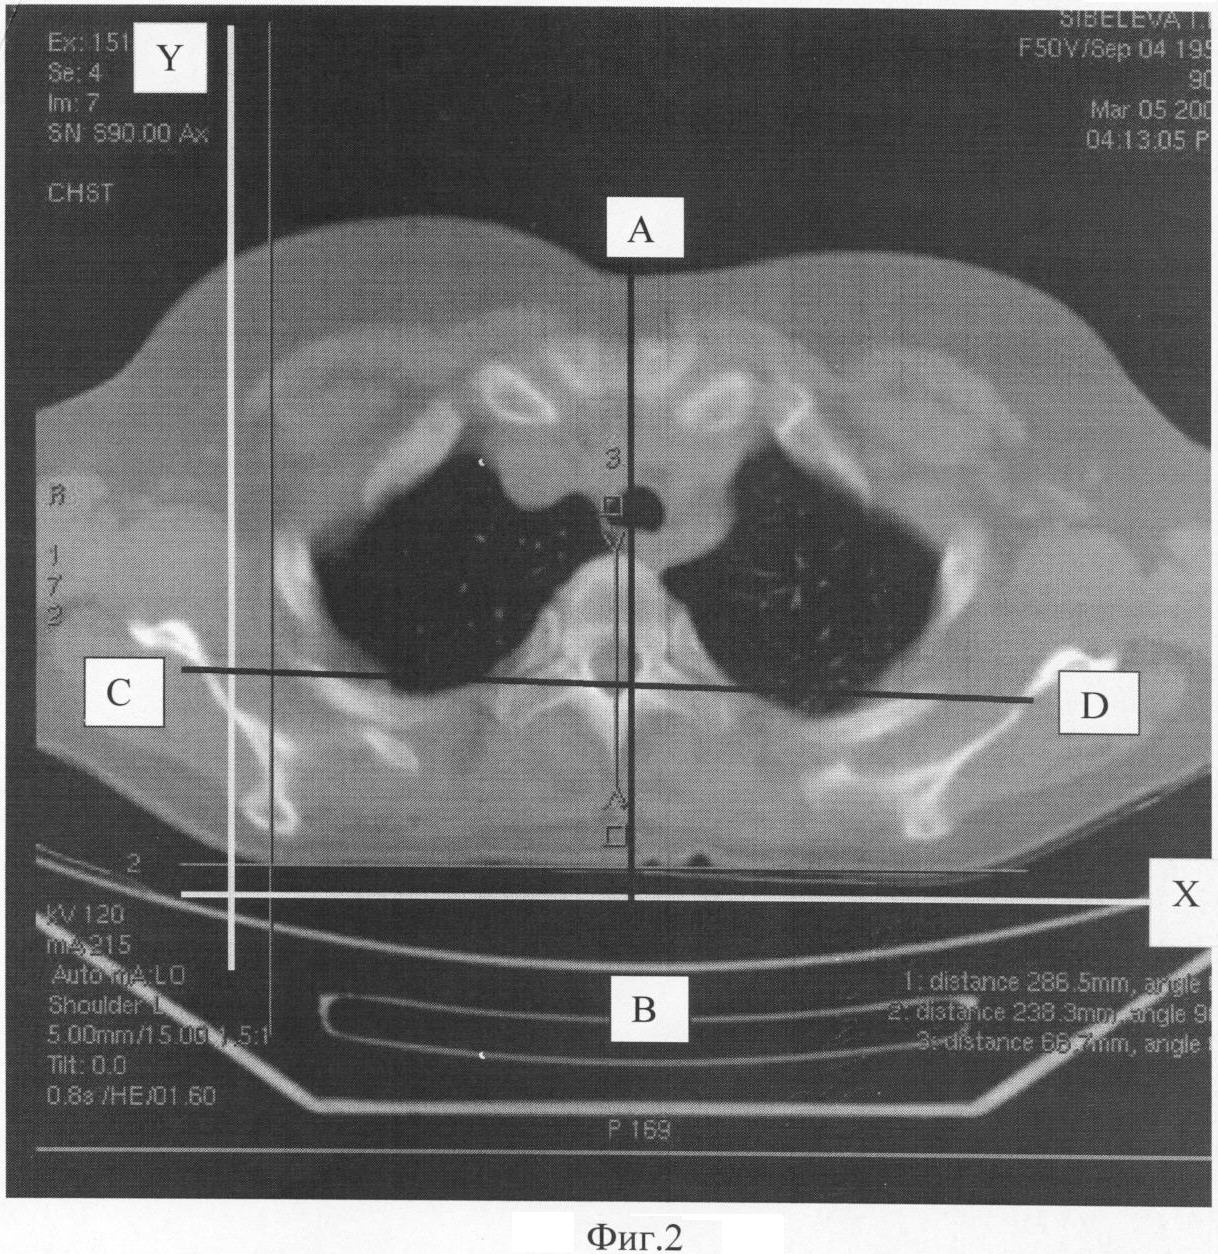

На фиг.2 представлен КТ срез на уровне тела Тh3.

Больному тяжелой формой коксартроза в диагностическом плане выполняют КТ таза на уровне подвздошно-крестцовых сочленений и КТ на уровне тела Тh3, затем на КТ срезе на уровне подвздошно-крестцовых сочленений проводят линию CD во фронтальной плоскости через передние края подвздошно-крестцовых сочленений (фиг.1) и линию АВ в сагиттальной плоскости через середину остистого отростка и тел S1-S3 (фиг.1), а на КТ срезе на уровне тела Тh3 проводят линию CD во фронтальной плоскости через передние края поперечных отростков тела Тh3 (фиг.2) и линию АВ в сагиттальной плоскости через середину остистого отростка и тела Тh3 (фиг.2), после чего измеряют величины углов, полученных при пересечении проведенных линий на уровне подвздошно-крестцовых сочленений и на уровне тела

Тh3 с линиями оси координат (X и Y), восстановленными на КТ срезах при помощи компьютерной программы КТ.

На томограмме на уровне тела Тh3 рентгенометрически определена величина ротации тела Тh3 и правой половины плечевого пояса кпереди и влево на 2°. На томограмме на уровне подвздошно-крестцовых сочленений определена величина ротации таза кпереди и влево на 8°. Разница величин ротации на уровне подвздошно-крестцовых сочленений и на уровне тела Тh3 составила 6°.